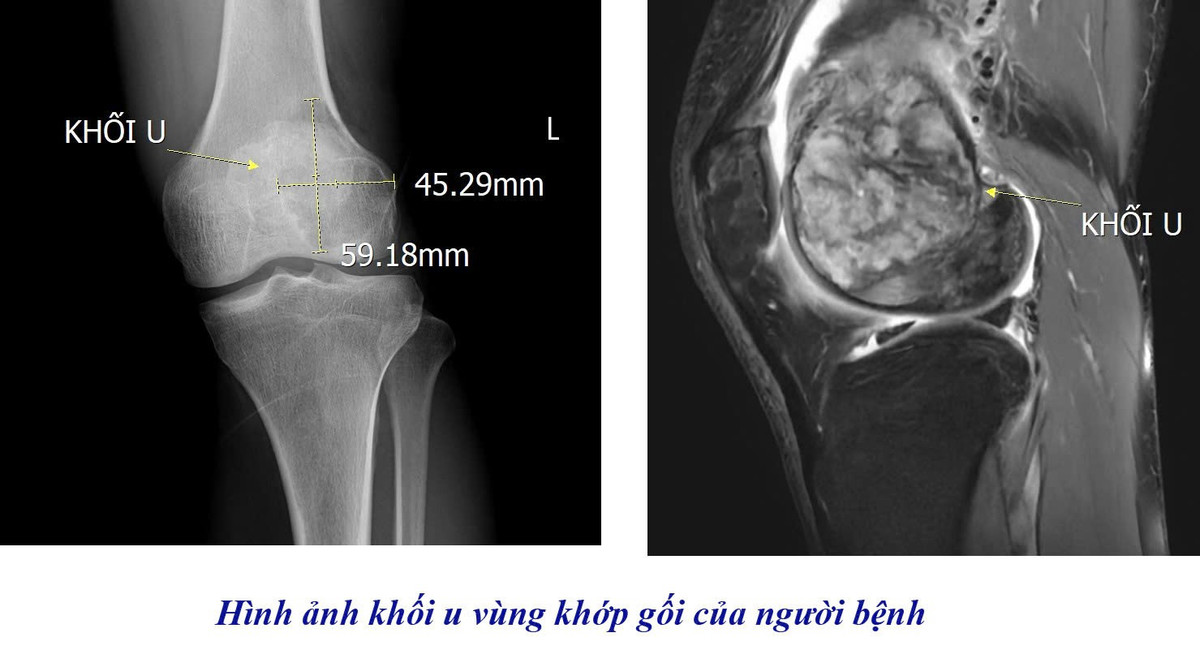

Qua thăm khám lâm sàng và chỉ định chẩn đoán hình ảnh, các bác sĩ đã tiến hành chụp cộng hưởng từ (MRI) khớp gối. Kết quả cho thấy người bệnh có khối u tế bào khổng lồ tại vùng khớp, cần được theo dõi và điều trị chuyên sâu nhằm tránh các biến chứng nguy hiểm.

U tế bào khổng lồ phát triển trong khớp gối bệnh nhân - Ảnh BVCC